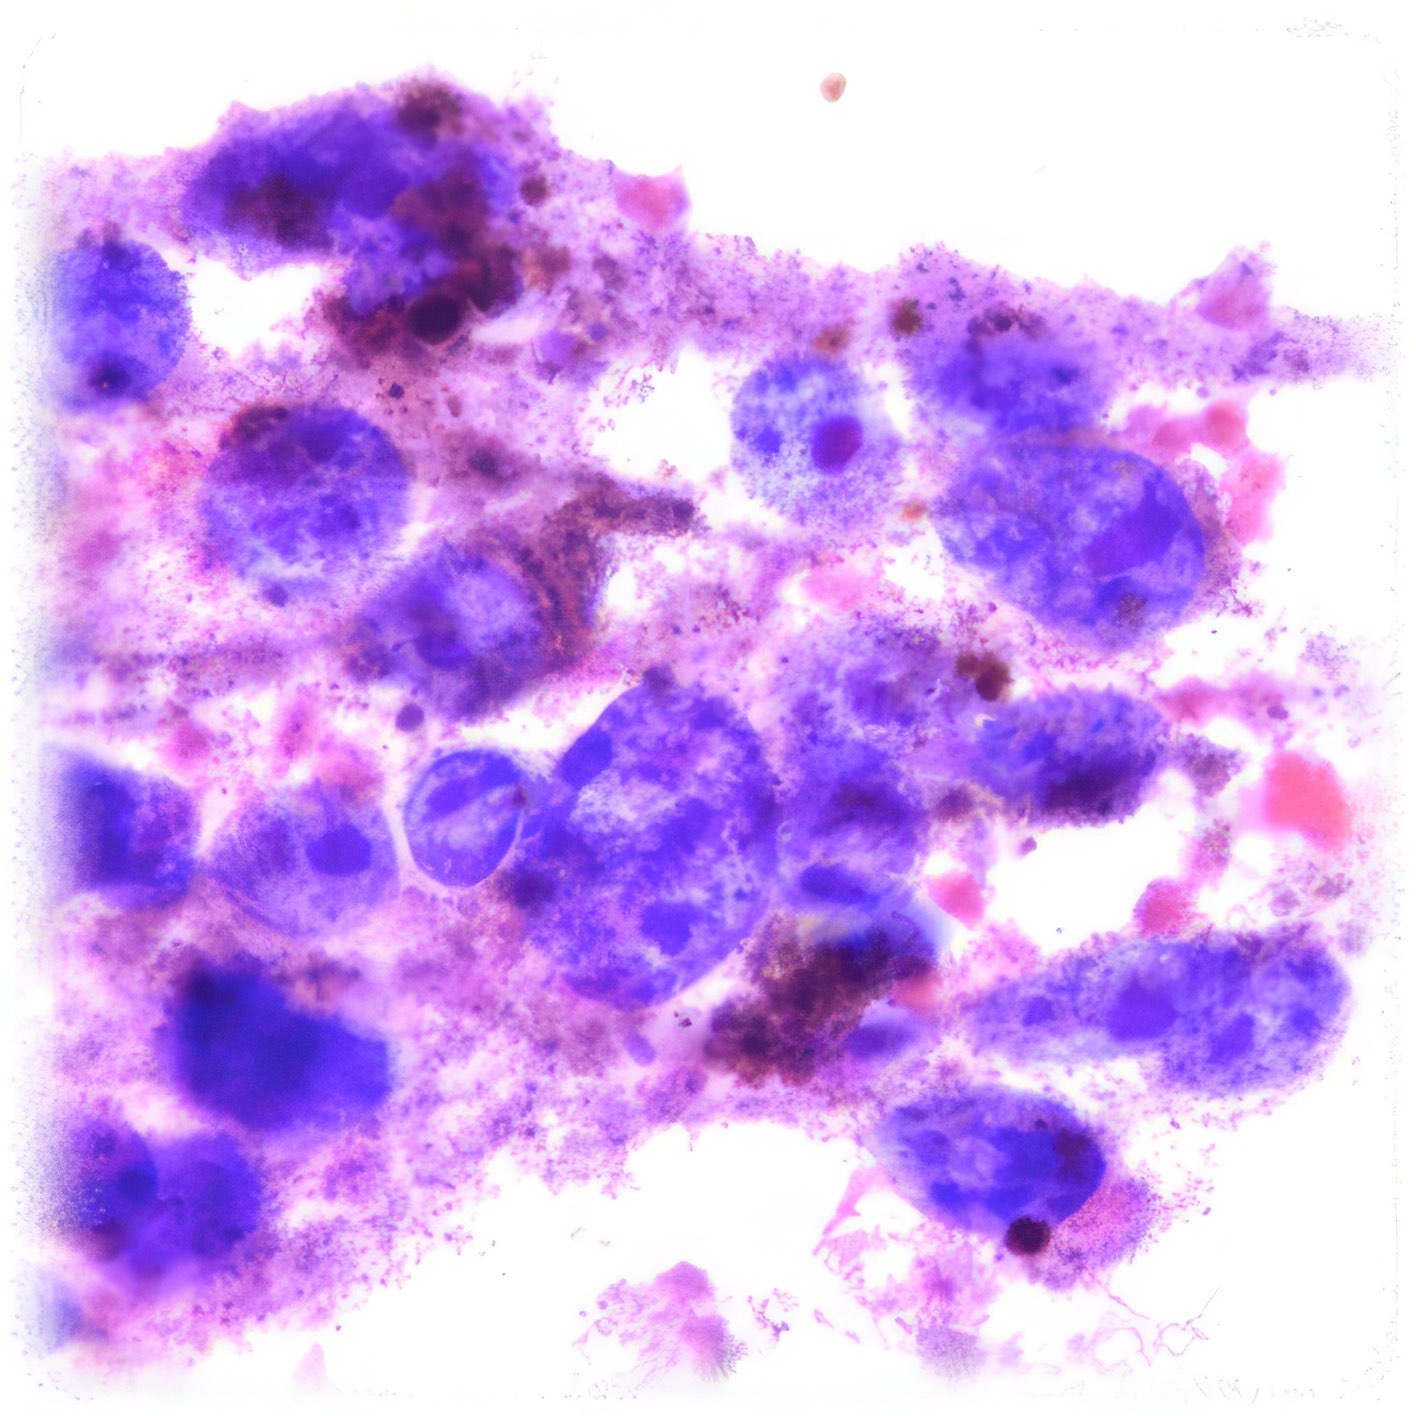

Abbildungen 2 - 4: Pap-Färbung, Obj. 40x.

Onkozytisches Adenom 1

Die zytologischen Abb. 2-4 zeigen dieselben Zellen. Das Zytoplasma ist breit fragil und enthält massenhaft feine eosinophile Granula. Die relativ grob strukturierten Kerne variieren in Größe, sind aber einheitlich rund, zeigen keine Kerben und enthalten einen gut erkennbaren Nukleolus.

Die eosinophilen Granula im Zytoplasma der Zellen entsprechen einer

dichten Ansammlung von Mitochondrien und gleichen damit den das Hormon

Calcitonin produzierenden para-follikulären Zellen der Schilddrüse. Diese

onkozytischen Tumoren wurden früher als Hürthle-Zell-Tumoren

bezeichnet.

Es gibt eine gut- und eine bösartige Variante (Adenom und Karzinom), die

zytologisch meist nicht zu unterscheiden sind und nur die Diagnose

„follikuläre Neoplasie, Bethesda IV“ erlauben. Auch histologisch ist

die Unterscheidung oft schwierig.

Makroskopisch handelt es sich im vorliegenden Fall um einen etwas über

2 cm messenden, von einer dünnen Kapsel eingeschlossenen Tumor (Abb.

5). Zytologisch sind weder Mitosen noch Kernkerben nachweisbar.

Histologisch konnten weder ein Kapseleinbruch (Abb. 6 u. 7), noch eine

Gefäßinvasion, noch papilläre Strukturen nachgewiesen werden. Das sind

Hinweise auf mehrjährige Rezidivfreiheit.